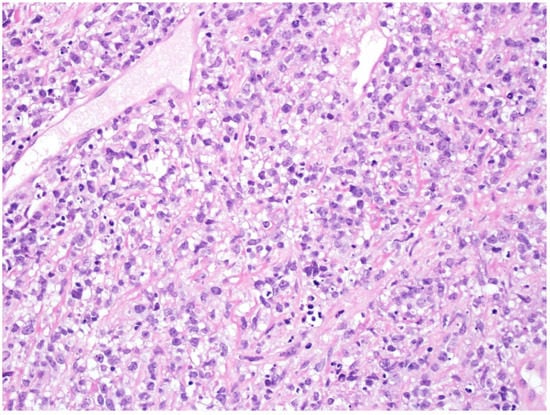

2. Diffuse Large B-Cell Lymphoma, Not Otherwise Specified

5. Diffuse Large B-Cell Lymphoma/High-Grade B-Cell Lymphoma with MYC and BCL2 Rearrangements

20. High-Grade-B-Cell-Lymphoma, NOS

- Rimsza, L.; Pittaluga, S.; Dirnhofer, S.; Copie-Bergman, C.; de Leval, L.; Facchetti, F.; Pileri, S.; Rosenwald, A.; Wotherspoon, A.; Fend, F. The clinicopathologic spectrum of mature aggressive B cell lymphomas. Virchows Arch. 2017, 471, 453–466. [Google Scholar] [CrossRef] [PubMed]

- Li, J.; Liu, X.; Yao, Z.; Zhang, M. High-Grade B-Cell Lymphomas, Not Otherwise Specified: A Study of 41 Cases. Cancer Manag. Res. 2020, 12, 1903–1912. [Google Scholar] [CrossRef]

- Kanagal-Shamanna, R.; Medeiros, L.J.; Lu, G.; Wang, S.A.; Manning, J.T.; Lin, P.; Penn, G.M.; Young, K.H.; You, M.J.; Vega, F.; et al. High-grade B cell lymphoma, unclassifiable, with blastoid features: An unusual morphological subgroup associated frequently with BCL2 and/or MYC gene rearrangements and a poor prognosis. Histopathology 2012, 61, 945–954. [Google Scholar] [CrossRef]

- Moore, E.M.; Aggarwal, N.; Surti, U.; Swerdlow, S.H. Further Exploration of the Complexities of Large B-Cell Lymphomas with MYC Abnormalities and the Importance of a Blastoid Morphology. Am. J. Surg. Pathol. 2017, 41, 1155–1166. [Google Scholar] [CrossRef]

- Ott, G. Aggressive B-cell lymphomas in the update of the 4th edition of the World Health Organization classification of haematopoietic and lymphatic tissues: Refinements of the classification, new entities and genetic findings. Br. J. Haematol. 2017, 178, 871–887. [Google Scholar] [CrossRef]

- Hüttl, K.S.; Staiger, A.M.; Richter, J.; Ott, M.M.; Kalmbach, S.; Klapper, W.; Biesdorf, A.-S.; Trümper, L.; Rosenwald, A.; Ziepert, M.; et al. The “Burkitt-like” immunophenotype and genotype is rarely encountered in diffuse large B cell lymphoma and high-grade B cell lymphoma, NOS. Virchows Arch. 2021, 479, 575–583. [Google Scholar] [CrossRef]

- Gonzalez de Villambrosia, S.; Bastos, M.; Palanca, J.M.; Cruz, J.G.; Navarro, J.-T.; Tapia, G.; Alonso, S.A.; Martin, A.; Blanco, O.; Abrisqueta, P.; et al. BCL2 translocation in high grade B cell lymphoma (NOS, DH/TH) is associated with reduced progression free survival. Leuk. Lymphoma 2022, 63, 101–108. [Google Scholar] [CrossRef]